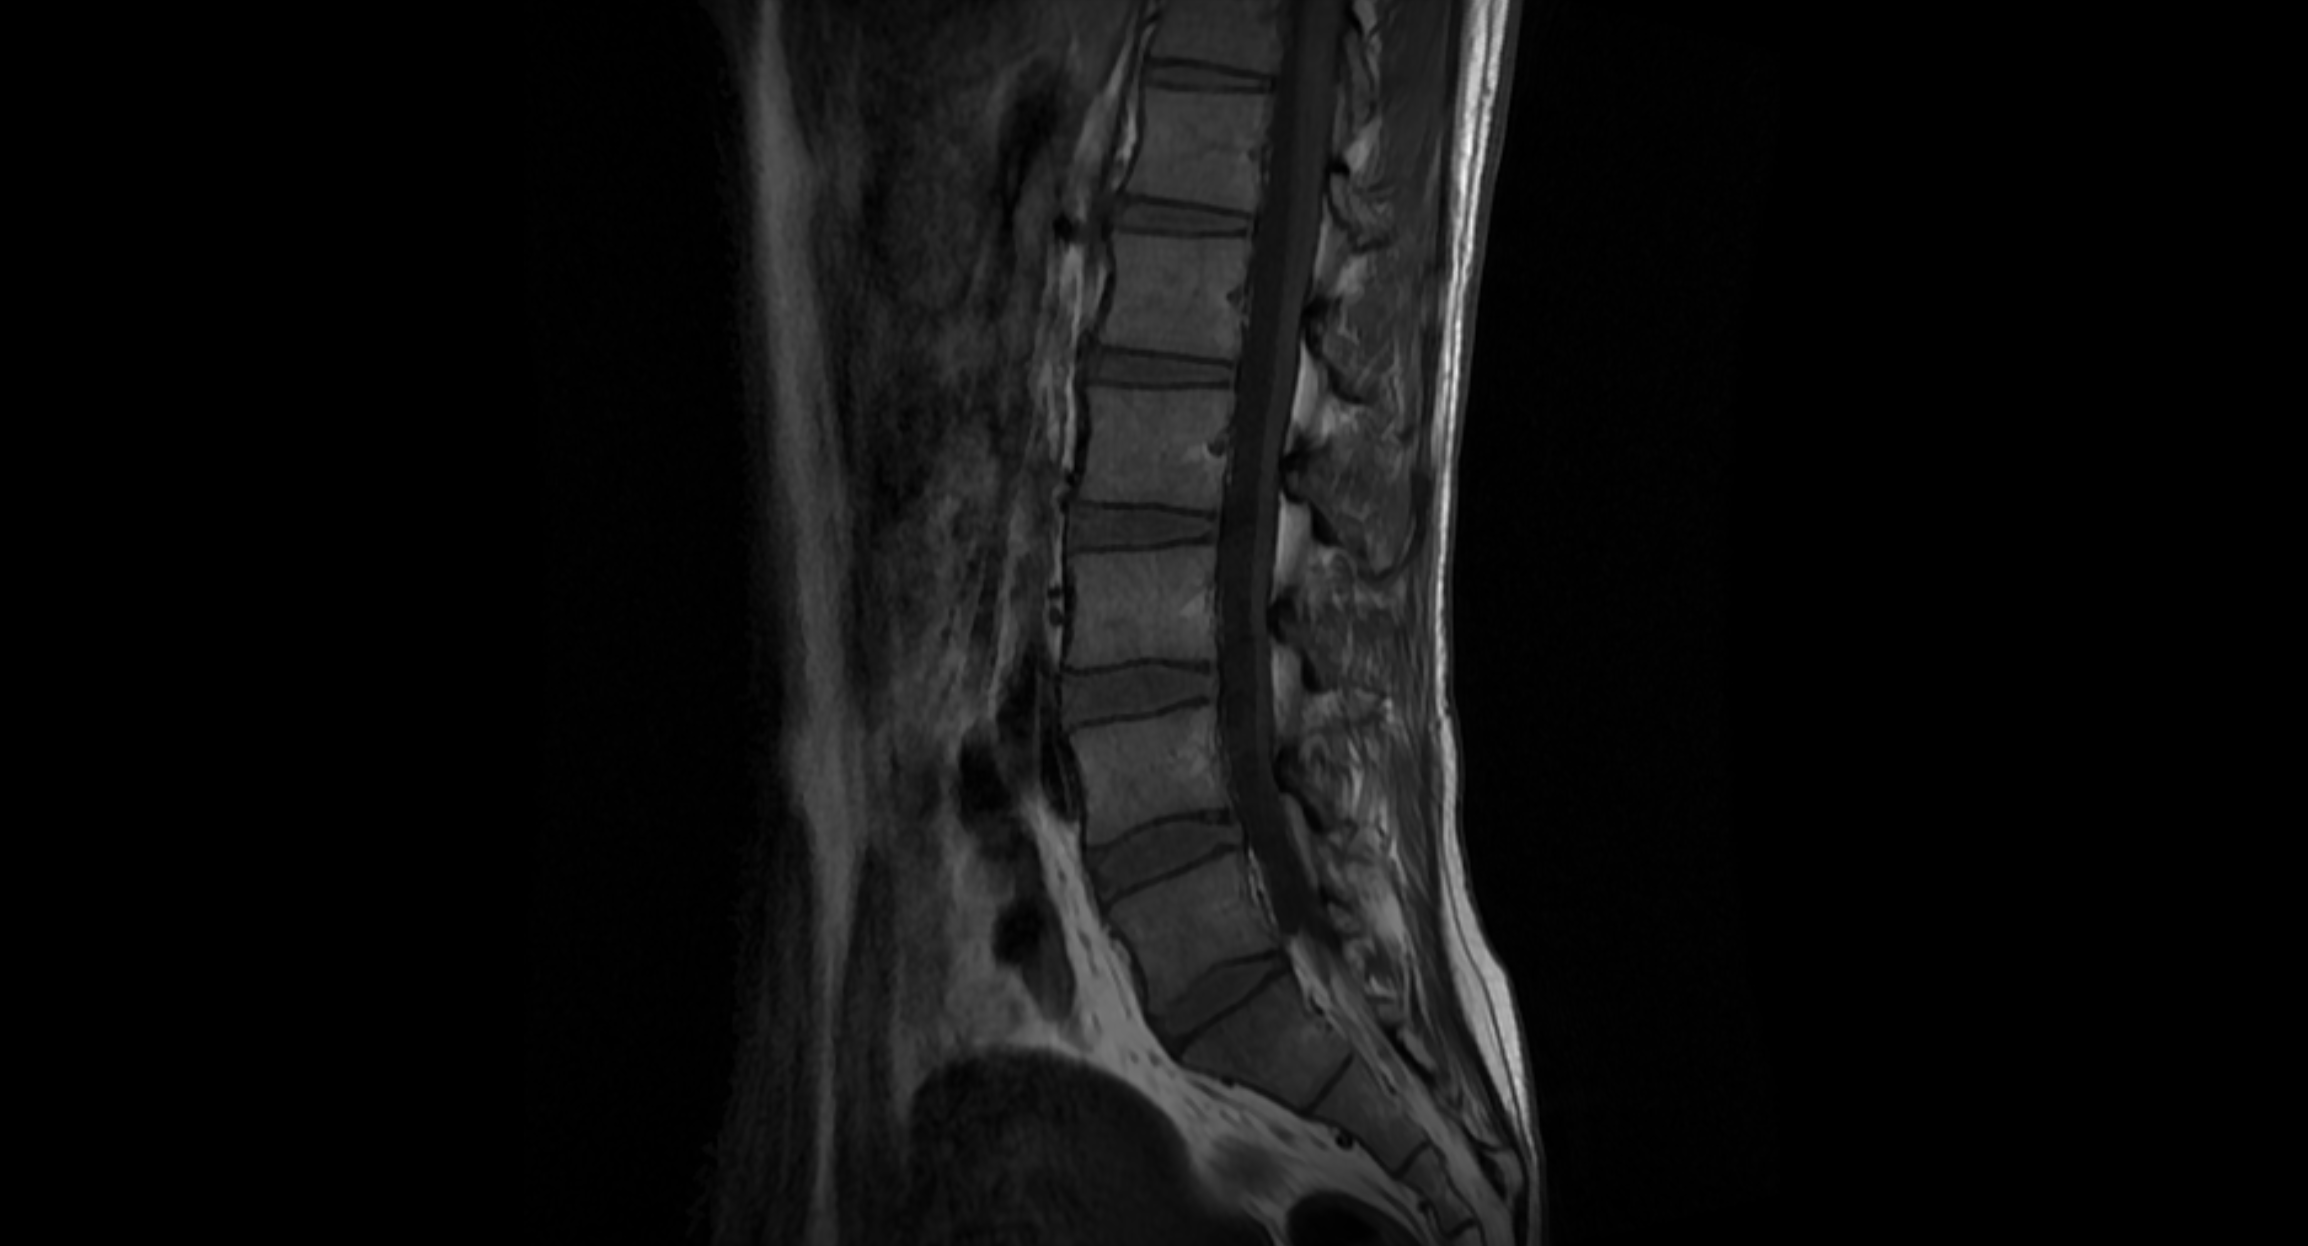

자, 여러분들은 해당 MRI를 보면 어떤 문제가 있는 걸로 보이시나요?

신기하게도 대부분의 사람들은 "괜찮은 허리로 보이는데?"라고 말합니다.

하지만 자세히 보면 요추 사이에 디스크가 후방으로 살짝 밀려있는 것을 볼 수 있습니다.

<요천추 MRI 판독 결과>

3번과 4번 사이에 "경도의 추간판 탈출증"

= 경도의 건초낭 압박

4번과 5번 사이에 "추간판 탈출증"

= 좌 신경공 좁아짐 의심

이게 참 신기한 게 전문가가 보면 다르게 보이나 봅니다.

판독 결과가 일주일 넘게 나오지 않길래, 해당 MRI 사진을 들고 여러 지인들에게 물어봤는데

다들 정상 아닌가?라고 말하길래 안심했다가

판독 결과 듣고는 멘붕 했습니다.

허리가 이 정도로 문제가 있다니...

MRI 결과를 보면 디스크가 살짝 탈출하여, 신경을 누르고 있습니다.